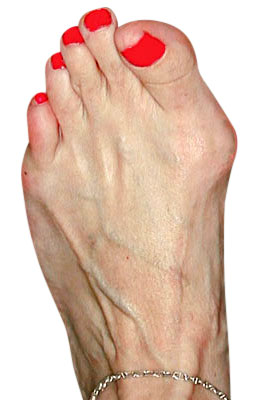

Minimally Invasive Bunion Surgery featuring the miniBunon™ System and Tailors Bunionectomy

Melissa is a 32-year-old businesswoman who could not be off her foot post-surgery, yet she had a severely painful bunion. We performed our miniBunon™ System (our trademarked minimally invasive bunion surgery) and had a dramatic correction with no downtime. Melissa continued to work after her bunion surgery and was back in shoes and full activity at 5 weeks. Melissa could not believe the results of her Bunionectomy resulting in no bony bump, no scar and amazing motion. “After” picture taken immediately following surgery. Note the bunion and bunionette (Tailor’s bunion) in the before picture.